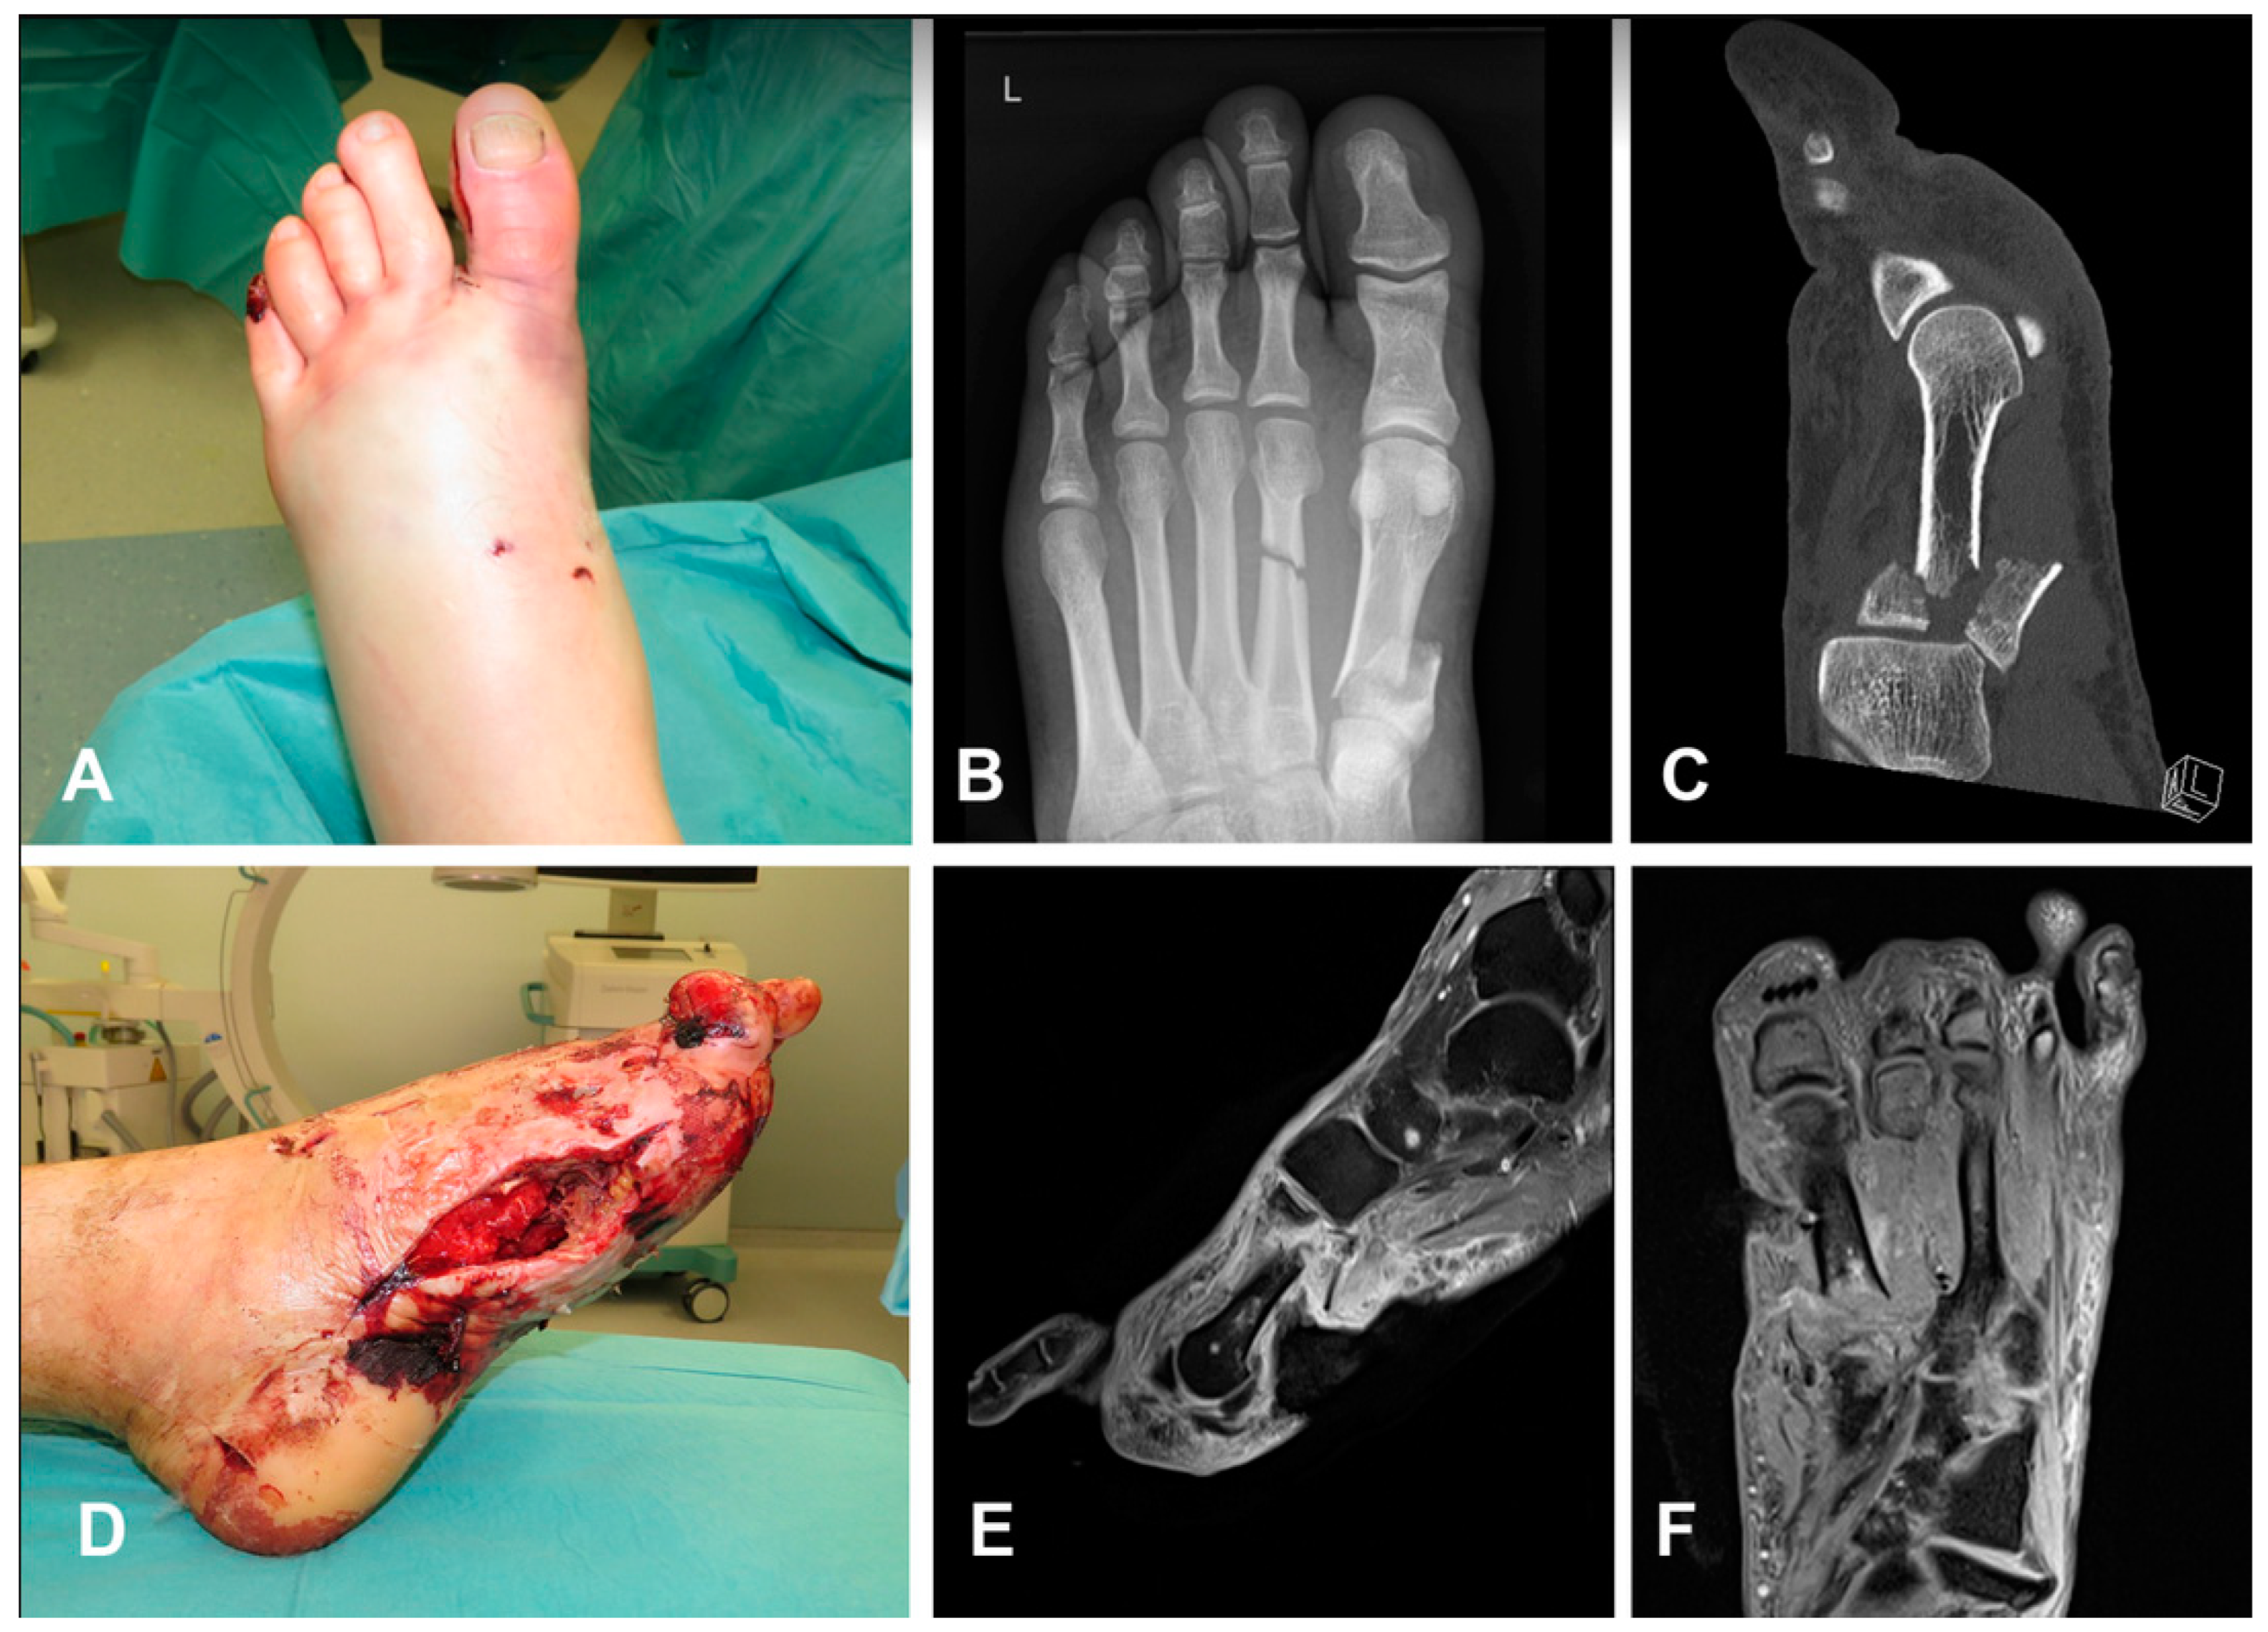

3.2.2. Case 2 (Patient No. 6)

| 2 | Ankle | Chronic OM | Bone gap following debridement | Monocortical 6 cm | Periosteal MFC flap | DIEP flap | 29 × 13 | Single flaps | Periosteal coverage the bone gap | None | 12 |